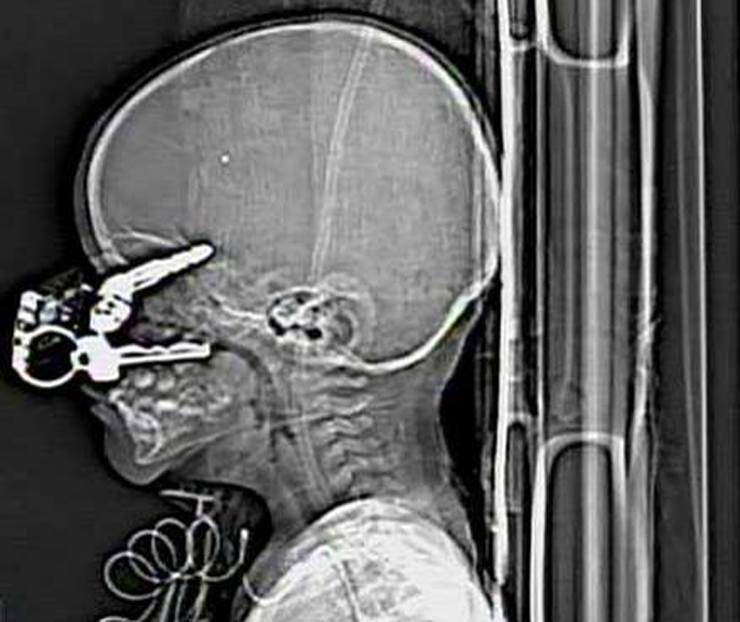

Ключи

На рентгеновском снимке 17-месячный ребёнок, который упал на ключи.